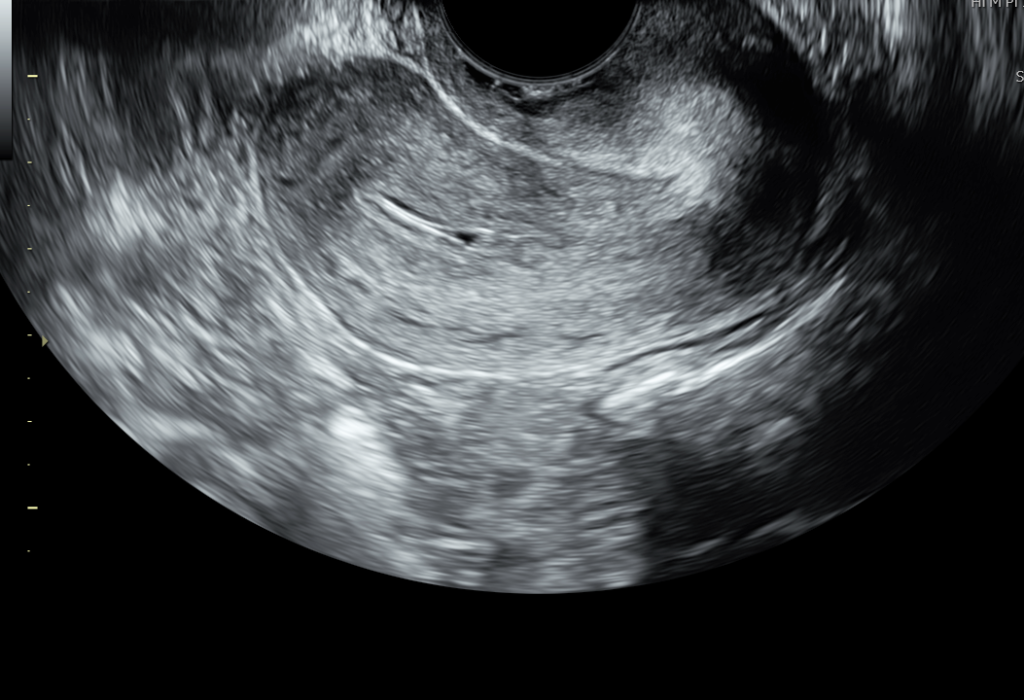

How Does the Scan Work?

Simple, safe, and usually done via transvaginal ultrasound for the best visuals.

2. Detailed Measurement

The doctor measures the thickness, shape, and texture of your lining.

You’ll also hear terms like “triple-line pattern,” which is a good marker for implantation.